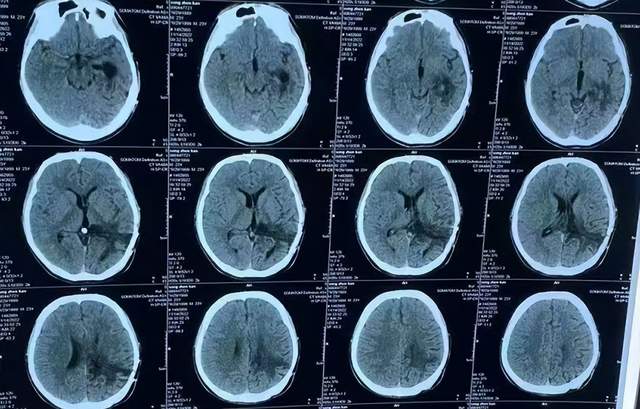

第2次出院后5个月即2022年6月初,再次出现头痛的症状,因左侧颞角再次增大,于2022年7月18日,第3次来到李小勇脑脊液科治疗。入院时:仅时有头痛。查头颅CT示左侧颞角扩张(图-33)。

图-33:2022年7月18日头颅CT

入院后3天即2022年7月21日,显微镜下颞角脉络丛切除术+分流管调整术,留置引流一根;术后查头颅CT示脑室内有2根管(图-34)。

图-34:2022年7月21日头颅CT

入院后11天即2022年7月29日(脉络丛切除术后8天),查头颅CT示引流术后状态(图-35)。

图-35:2022年7月29日头颅CT

入院治疗12天即2022年7月30日(脉络丛切除术后9天),给予拔除了原脑室腹腔分流管,查头颅CT示脑室内有一根管(图-36)。

图-36:2022年7月30日头颅CT

入院治疗21天即2022年8月8日(脉络丛切除术后18天),查头颅CT未见异常(图-37),患者身体无异常(图-38)。

图-37:2022年8月8日头颅CT

2022年8月22日(脉络丛切除术后32天),查头颅CT示颞角未见扩张(图-39),给予夹闭引流管。

图-39:2022年8月22日头颅CT

夹闭引流管14天后即2022年9月5日(脉络丛切除术后46天),查头颅CT示未见异常(图-40)。

图-40:2022年9月5日头颅CT

夹闭引流管15天后即2022年9月6日(脉络丛切除术后47天),给予拔除了脑室外引流管,当天查头颅CT示脑室基本正常(图-41);患者身体无异常。

图-41:2022年9月6日头颅CT

拔除了脑室外引流管后6天即2022年9月12日, 查头颅CT示未见异常(图-42);身体一切正常,于2022年9月16日出院。

图-42:2022年9月12日头颅CT

出院后3个月即2022年11月,在当地医院查头颅CT示无异常(图-43);本人叙述身体一切正常。

图-43:2022年11月头颅CT